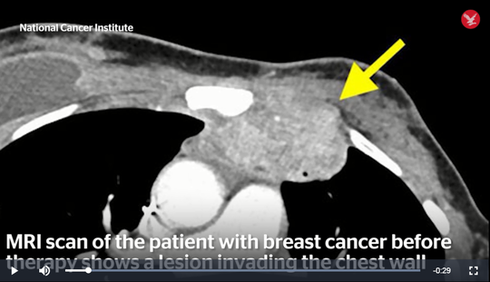

Khối u rất lớn trong ngực bà Perkins thể hiện trên phim MRI - ảnh cắt từ clip của NCI |

Kết quả là hệ miễn dịch của bà Perkins đã phá hủy rất nhanh chóng khối u chính lẫn các điểm di căn và tự làm bà khỏi bệnh. Hiện nay, sau 2 năm, các bác sĩ đã kiểm tra lại nhiều lần và không phát hiện bất kỳ dấu hiệu nào khác của bệnh ung thư trong cơ thể bà.